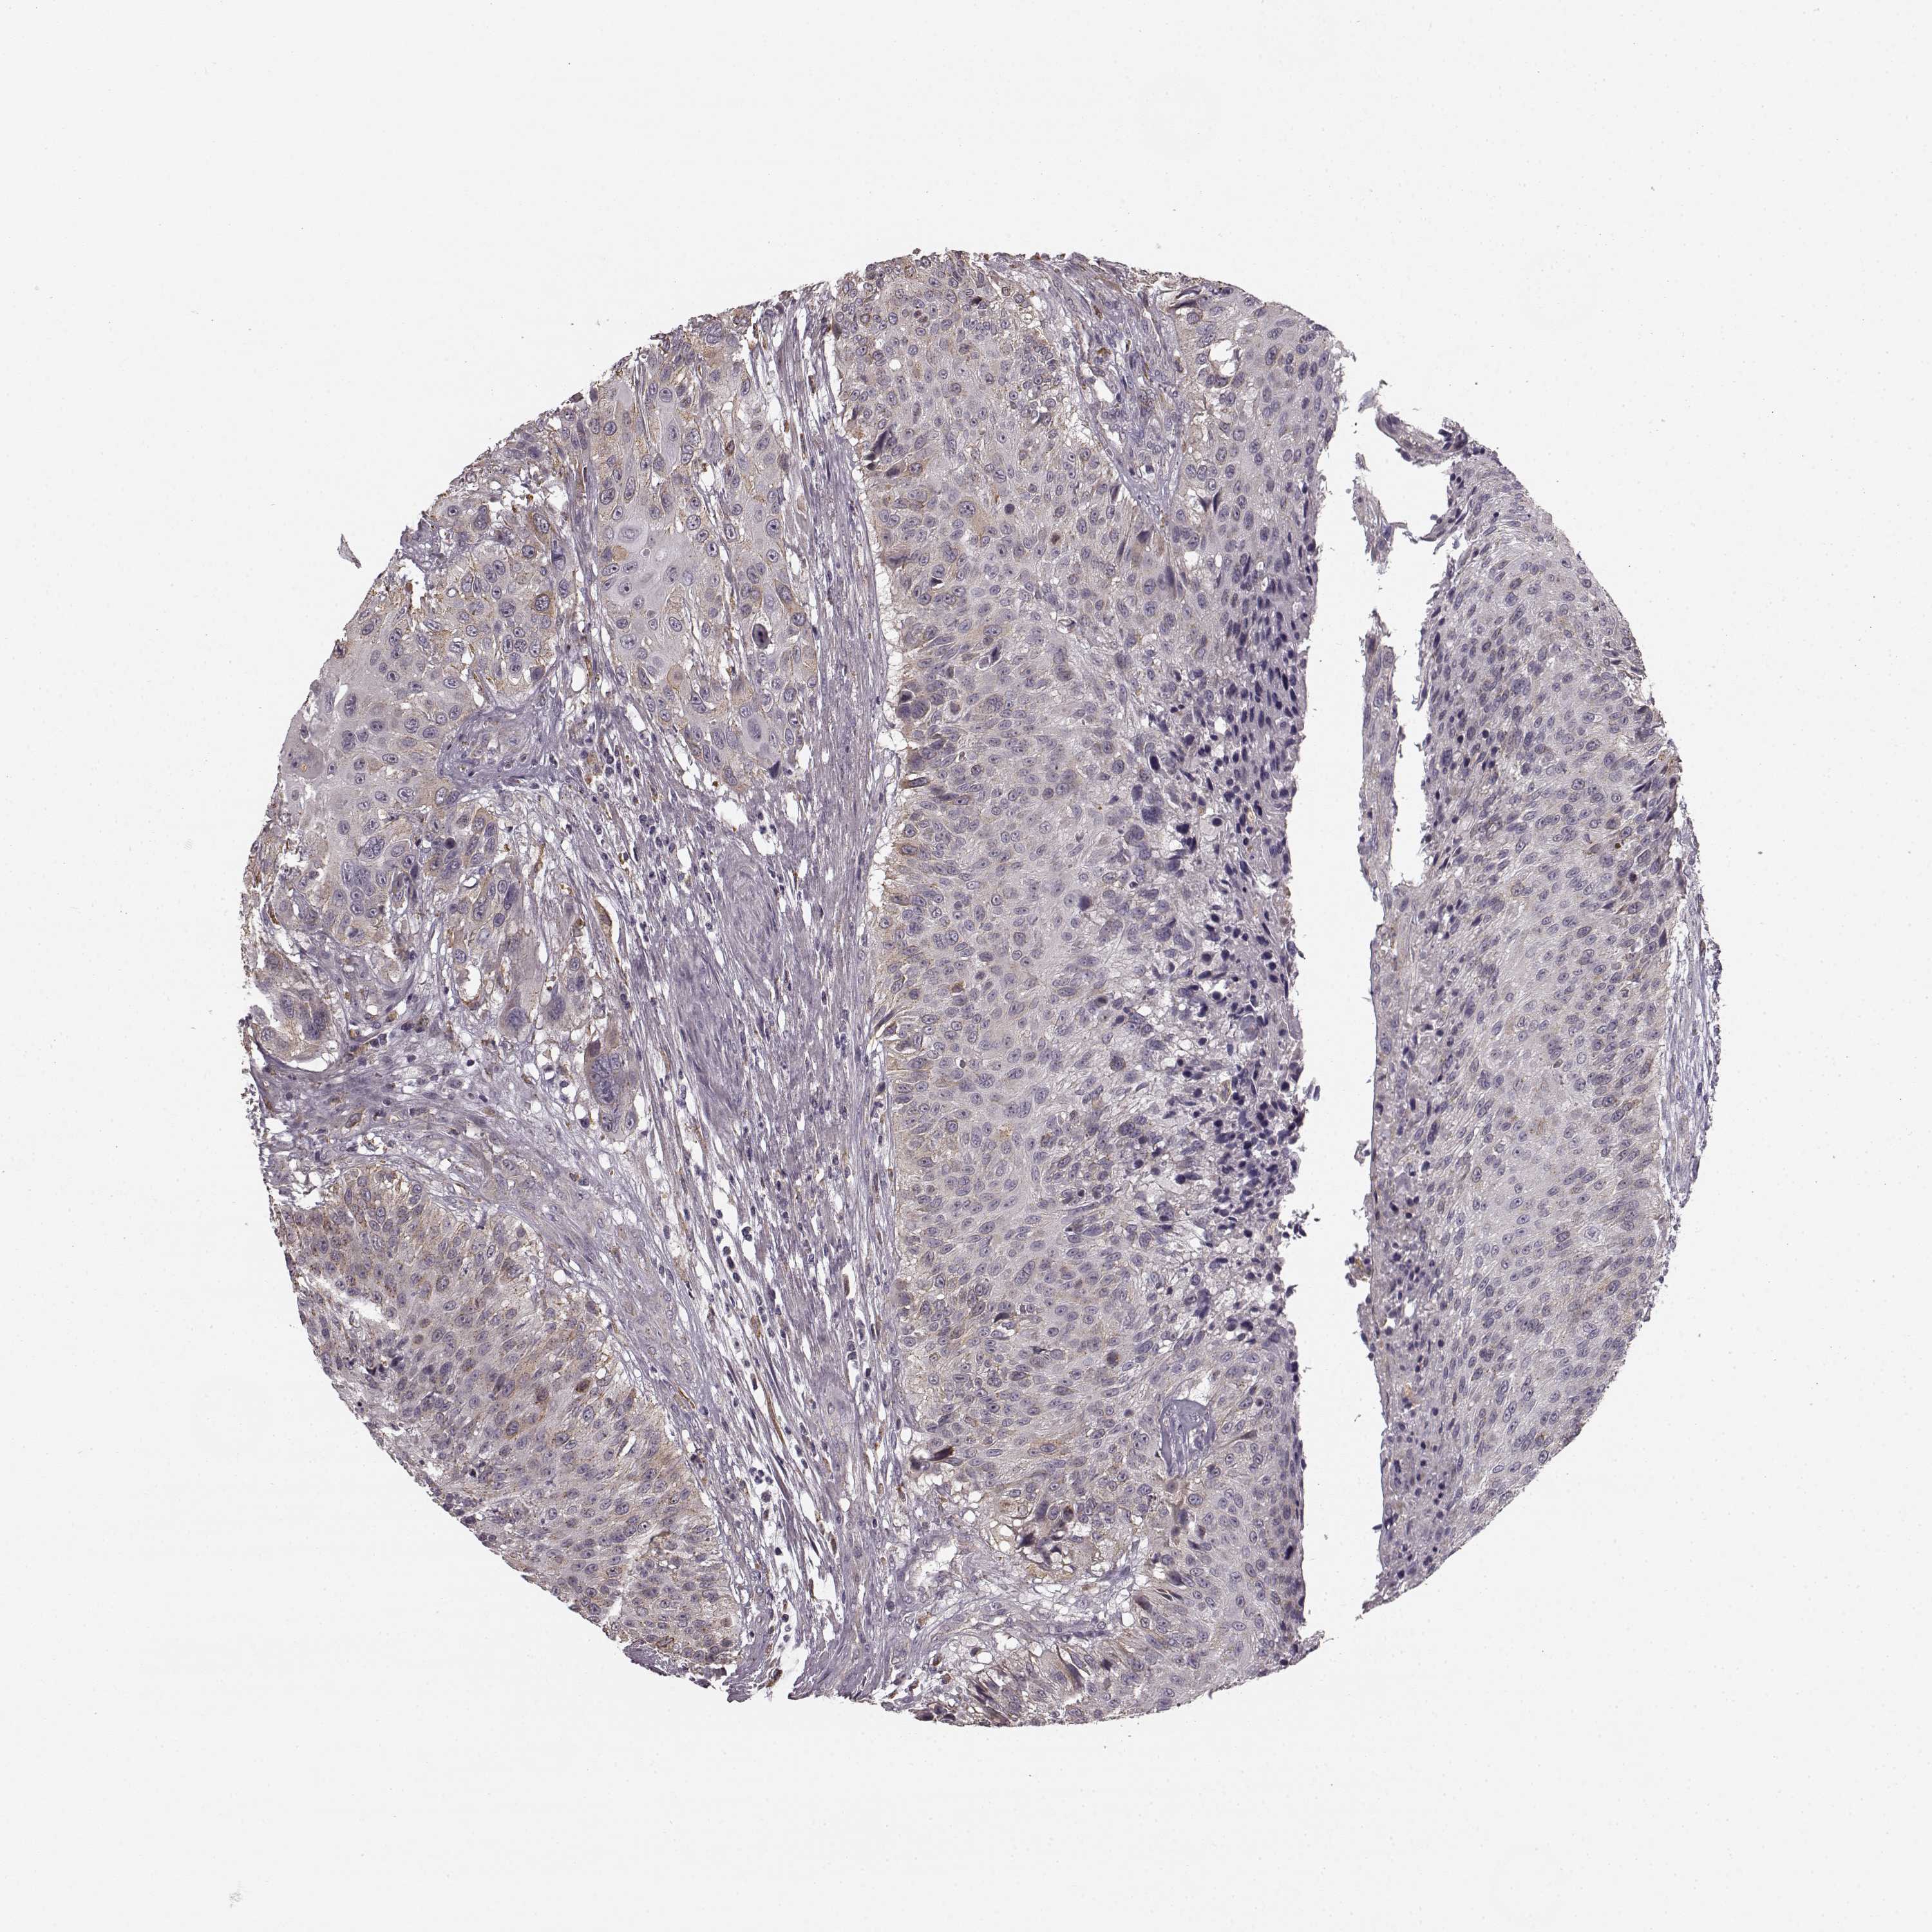

UROTHELIAL CANCER - Protein expressioni

A mouse-over function shows sample information and annotation data. Click on an image to view it in a full screen mode. Samples can be filtered based on level of antibody staining by selecting one or several of the following categories: high, medium, low and not detected. The assay and annotation is described here.

Antibody stainingi

Antibody staining in the annotated cell types in the current human tissue is reported as not detected, low, medium, or high, based on conventional immunohistochemistry profiling in selected tissues. This score is based on the combination of the staining intensity and fraction of stained cells.

Each image is clickable and will lead to virtual microscopy that enables deeper exploration of all samples and also displays staining intensity scores, fraction scores and subcellular localization as well as patient and tissue information for each sample.

Antibody HPA040025

Antibody CAB002433

Urothelial carcinoma, High grade

Urothelial carcinoma, NOS

Urothelial carcinoma, Low grade